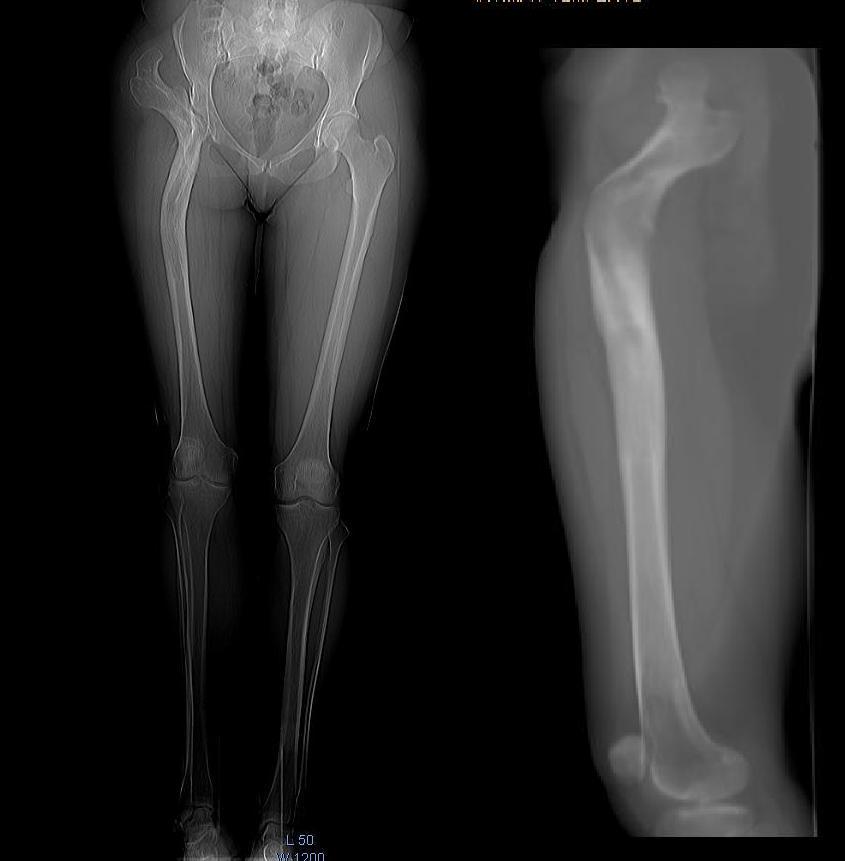

Пациентка  41 год, нормального телосложения, правосторонний

диспластический коксартроз  Crowe IV состояние после опорной остеотомии

по Илизарову более 20-ти лет назад.

Относительное укорочение правой н.к.  2-3 см.  Абсолютное периудлинение

правого бедра 5-6 см (по данным КТ). Планируем укорачивающую резекцию

бедра с транспозицией большого вертела. В литературе широко  описаны

аналогичные случаи  эндопротезирования после остеотомии по Schanz,

однако в отличие от Илизаровской остеотомии,  без абсолютного

переудлинения бедра и без деформаций канала на уровне с/3 диафиза.  Ув.